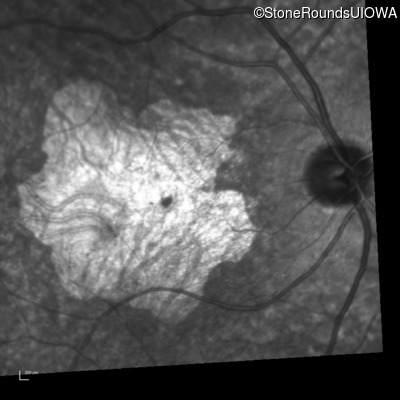

Infrared Fundus Photograph - Right - 20/40

Exemplar